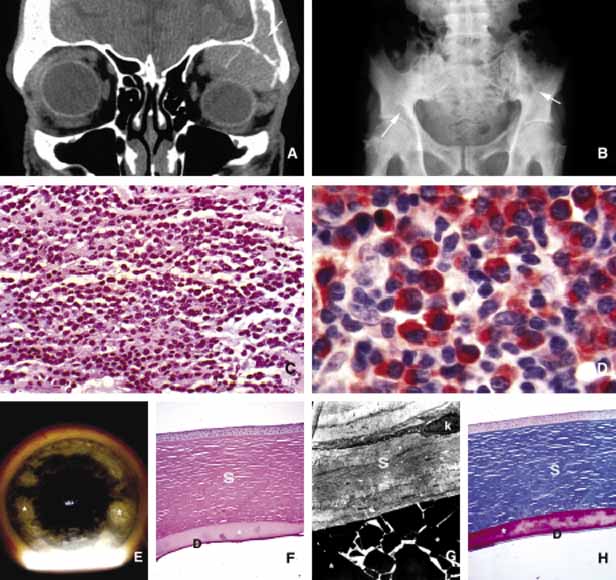

ANOPHTHALMOS/MICROPHTHALMOS When the globe is abnormally developed, microphthalmos, congenital cystic eye, and extremely rarely, anophthalmos occur. Microphthalmos usually occurs as a unilateral condition and in approximately 10% of cases it is associated with other craniofacial malformations including agenesis of the corpus callosum, polymicrogyria, and mid-line arachnoidal cysts. Microphthalmos may be seen as a part of several genetically determined neuronal migration disorders such as Walker-Warburg syndrome, Aicardi syndrome, and Fukuyama congential muscular dystrophy.9,10 In cases of microphthalmos and anophthalmos the orbit may be well formed but does not develop to a full adult volume. The mechanism by which the presence of the globe effects the growth of the orbit is not well understood. Microphthalmos may be associated with a colobomatous cyst as a result of the abnormal closure of the embryonic optic fissure leading to the prolapse of neuroectodermal tissues into the orbit (Fig. 1) This cystic structure may increase rapidly in size to overshadow the abnormal globe and may be confused with a neoplasm. When cystic lesions in the orbit are suspected imaging studies should be performed not only to look for other intracranial abnormalities but also to establish the possible connection of the cyst to the colobomatous globe versus to abnormally formed meninges.11 Macrophthalmos (buphthalmos) may also rarely develop as a congenital anomaly in patients with Sturge-Weber syndrome and rarely in neurofibromatosis type I. ORBITO-CRANIAL MALDEVELOPMENTS Cephalocele results from the extension of maldeveloped CNS tissues including meninges (meningocele), brain parenchyma (encephalocele), and the combination of the two (meningoencephalocele) into the orbital cavity.12,13 Intraorbital cephaloceles may develop anteriorly at the suture lines of orbital bones or posteriorly extending into the orbit from orbital fissures and the optic canal. Depending on the combination of these herniations they contain brain and/or meningeal tissues (Fig. 1). Aberrant fibroglial tissue has also been described in the orbit.14 Hamartoma is a tumor-like proliferation of tissues that normally exist at a given body location. The best examples of orbital hamartomas are the vascular hamartomatous lesions that are composed of vascular elements including capillary endothelial cells, distended or collapsed cavernous blood and lymph vessels, tortuous arterial and venous channels with or without anastomoses, etc. Other examples of hamartomatous orbital tumors include neurofibroma and lipomatous hamartoma.15 Choristoma, however, is a tumor-like proliferation of tissues that are not normally present at a given body location. The most commonly encountered example of orbital choristoma is a dermoid.16 Dermoids that present with many varieties result from the entrapment of epithelial structures at the site of closure of fetal fissures. Superficial dermoid cysts occur primarily subcutaneously anterior to orbital septum or within the anterior orbit. If the cyst wall is made of epidermis without dermal tissues, it is classified as an epidermoid cyst. These lesions are occasionally lined by conjunctival or pseudostratified respiratory epithelium.17 The superficial lesions must be distinguished from deep orbital dermoids that are usually rounded, encapsulated tumors filled with fatty materials, keratin, and dermal structures such as hair particles. Histopathologically the dermoid wall is lined by keratizing squamous epithelium with dermal appendices including hair follicles and sebaceous and eccrine glands.18 Most of the dermoids are well outlined by ultrasonography because of their anterior location thus making CT or MRI rarely necessary.19 If the dermoid is unusually large or located at the frontal zygomatic suture, CT is necessary to document the relationship of the lesion to the bone before surgical intervention. Rarely, dermoids at the fronto-zygomatic suture may develop dumbbell-shaped lesions partially within the orbit and partially extending into the temporal fossa.20,21 Unusually large superior orbital dermoids particularly those that leak and create granulomatous reaction within adjacent soft tissues may erode the bone and extend into the frontal sinus or the cranium (Fig. 2). ORBITAL TERATOMA Teratoma is a germ-cell tumor that contains tissues derived from endoderm, ectoderm, and mesoderm22 (Fig. 1). Therefore, these lesions may contain skin, bowel, lung, brain, thyroid, cartilage, and bone tissues. Most teratomas develop unilaterally and in girls. A majority of these congenital tumors are benign. Occasional reports have documented malignant transformation within orbitocranial teratomas.23 However, these benign tumors continue to grow after birth because of the collection of secretions from different tissues into the partially cystic spaces of the tumor. Some teratomas create massive proptosis and most can only be treated by exenteration. However, some of these lesions have recently been reported to be removed surgically with preservation of the globe and other vital orbital structures. TRAUMA Mechanical Injury Orbital injuries result from the absorption of kinetic energy that occurs whenever the orbital tissues contact an object moving at a different speed.25 The orbital rim is capable of absorbing a considerable amount of kinetic energy without being fractured. Yet, a variety of impact forces striking the orbit may result in fractures in different areas.26 The absorption of the kinetic energy by an orbital bone may lead to contusion and/or laceration of the skin and superficial soft tissues, local deformation of the adjacent structures, globe, orbital soft tissues and bones and increases pressure in the orbital cavity. A common end result of an orbital impact is the fracture of the floor and/or the medial wall (lamina papyracea)27 (Fig. 3). Fractures of other orbital bones occur less often. Foreign bodies may be introduced into the orbit at the time of injury and may cause secondary problems depending on the nature and the location of the foreign body.28 Some foreign bodies such as copper may cause tissue necrosis and degeneration (chalcosis), and others particularly organic matter, may carry organisms such as bacteria and fungi into the orbital tissues and cause secondary infections29 (Fig. 3). Once the fracture of an orbital bone occurs, it may produce sharp edges to lacerate adjacent soft tissue structures including the globe, optic nerve, other nerves, muscles, and vessels.30 Depending on the damage of the particular tissue, functional deficit results. Another issue to deal with in an injured orbit is the development of hematoma, hematic cyst, and cholesteotoma. Hemorrhage in the orbit may occur spontaneously without any physical exertion in healthy individuals. Although terminology is not very strict, hematoma usually refers to a localized collection of blood within orbital soft tissues that develops secondary to trauma. When the blood collection within the orbit becomes organized and surrounded by a thin pseudocapsule, it is known as a hematic cyst31 (Fig. 4). If the hemorrhage develops within an existing lymphatic or vascular tumor, these lesions are known as blood cysts or “chocolate” cysts.32 Hematic cyst consists of a localized collection of blood surrounded by a nonepithelium-lined thin fibrous capsule.33 These lesions usually develop within 1 to 2 weeks of orbital trauma but chronic cases may occur up to 20 years after orbital injury.34,35 They may reach to a size causing proptosis, extraocular motility disturbance, compression on the globe and optic nerve, that can easily be detected with ultrasonography, CT, or MRI. Hematic cysts may develop within the muscle cone or in the extraconal orbital locations.33–36 These cysts are lined by fibrovascular tissue at the periphery and contain degenerated erythrocytes, protein debris, and cholesterol crystals. In many instances the thin nonepithelial lining is adherent to the adjacent structures with fibrous tissue. Cholesteatoma is another cystic lesion that is confined within a “pseudowall” without an epithelial lining.37 Cholesteotomas are usually located in the superior lateral orbit within the lacrimal gland fossa. Imaging studies may show a cystic, semi-cystic, or a solid lesion within the diploe of the bone or within the orbital soft tissues, with or without erosion of the adjacent bone.38 Histopathologically the lesion is composed of cholesterol clefts, hemosiderin, and hematoidin granules, other blood breakdown products and fibrin surrounded by a mixed lymphohistiocytic infiltrate and multinucleated foreign body giant cells.39 On imaging studies these lesions appear as unilocular rounded masses with destruction of the adjacent frontal and zygomatic bones. Although bone involvement in general implies malignancy, the sclerosing character of the bony destruction in choleosteoma, which is best seen in bone window images, favors a benign lesion. Although bone destruction also makes one think along the lines of metastatic tumors, one should also consider benign lesions such as brown tumor, aneurysmal bone cyst, and ruptured dermoid. Multiple cuts of the frontal bone should be examined to rule out the possibility of intracranial extension. Osteomyelitis of the orbital bones evolving as a complication of paranasal sinusitis is another entity that should be considered in the differential diagnosis of cholesteotoma. In osteomyelitis the bone infection extends into the periosteal space and beyond. Precise delineation of the lesion can be performed with CT and MRI particularly in combination with bone SPECT, a sensitive technique used to detect osteomyelitis within cranial and orbital bones.40 Mucocele Although a commonly encountered space occupying lesion in the orbit, mucocele is technically not a neoplasm. It is a cystic cavity lined by pseudostratified respiratory epithelium prolapsing into the orbit from a paranasal sinus, most commonly the frontal followed by the ethmoidal sinus (Fig. 5). Primary mucoceles develop as a result of an inflammatory obstruction of the ostium of the paranasal sinuses. Secondary mucoceles, however, are most commonly seen after orbital trauma and surgery; they may also develop secondary to neoplasms of paranasal sinuses and nasopharynx. If there is a superimposed infection, the lesion is referred to as pyocele. The mucocele develops as a well delineated cystic structure originating from a paranasal sinus. Depending on the location, it may compress orbital structures including extraocular muscles, optic nerve, and the globe.41 Clinical presentation of the mucocele is usually with globe displacement and/or proptosis, extraocular motility deficiency, particularly in the direction of the sinus extension into the orbit, and other compressive symptoms.42 The crepitant or calcified hard wall of the mucocele may be palpated underneath the superior or medial orbital rim. Mucoceles in general, are rare in children, however, a unique variant, ethmoidal mucopyocele, is known to occur in the medial canthal area, with lateral displacement of the globe. On CT, mucoceles present as hypointense, expanding masses originating from the paranasal sinuses. Early in their development these lesions are small, mucous-containing cysts. Later they are characterized by crescent-shaped and thinned remodeling of the bony walls of the orbit and sinuses.43 On MRI, mucocele presents with different appearances depending on the amount of free water within its luminal contents. When the intraluminal mucous becomes inspissated, the signal intensity in both T1 and T2 images decrease, getting closer to normal air content of the sinus.44 Treatment of mucocele is surgical excision. Other injuries with toxic chemicals and radiation are known to damage orbital tissues.45–47 VASCULAR MALFORMATIONS Arteriovenous Fistula Orbital arteriovenous (AV) fistulas are established as a result of abnormal flow between the arteries and veins. These lesions can be divided into three basic types: carotid cavernous, dural and orbital AV fistulas. Carotid cavernous fistula is usually traumatic but may also develop secondary to a rupture of an aneurysm particularly in elderly atherosclerotic patients. These fistulas commonly develop between an intracavernous segment of internal carotid artery and cavernous sinus and shunt arterial blood into superior ophthalmic vein.48 Dural cavernous fistulas, however, develop between small meningeal branches of internal/external carotid artery and the cavernous sinus. These small vessels that have thin walls that may rupture spontaneously particularly in hypertensive individuals, secondary to minor trauma and maintain a low blood flow. Orbital AV fistulas usually develop secondary to traumatic rupture of the ethmoidal artery into the orbital venous system. This type of fistula maintains a low blood flow. Clinical findings of AV fistulas include rapidly developing proptosis, edema of the conjunctiva and eyelids, dilatation and tortuosity of the conjunctival and episcleral vessels, and secondary glaucoma. Most of these cases are diagnosed with imaging procedures including CT, MRI, angiography, color Doppler ultrasonography, and catheterized angiography.49 Current treatment of these lesions is embolization via catherization.50 Morphologic data are limited to autopsy material because most patients with AV fistulas do not undergo biopsy procedure. These lesions show irregular, malformed arteries and veins with abnormal elastic and muscular layers and secondary endothelial cell proliferation. Approximately half of the low shunt fistulas close spontaneously;51 therefore, it is best to follow-up some of these patients conservatively if they do not have severe symptoms. Orbital Varix Orbital varix is a rare vascular lesion with questionable histopathogenesis. The absence of valves in the orbital venous system and the weakening of venous wall may lead to pooling and stasis of blood resulting in distention of the venous channel with thrombosis. In gross appearance, the varix is a distended vein containing a canalized or uncanalized thrombus.52,53 Histopathologically varix consist of irregular vascular channels lined by endothelial cells. In chronic lesions, the blood vessel walls irregularly thicken with fibrosis and deposits of chronic inflammatory cells mixed with deposits of calcium and hemosiderin pigment are seen. Orbital varices are divided into primary and secondary types. The primary orbital varix is confined to the orbit as an isolated lesion without any connection to other A-V malformations. The secondary orbital varix, however, develops as an extension of an intracranial AV malformation that shunts blood to the orbital venous system causing the venous channels to distend secondarily.54 Management of orbital varix consists of total surgical excision when possible and/or endovascular embolization. | |||||||||||||||||||||||||||||||||||||||

For the sake of simplicity, orbital neoplasia are divided into three major subgroups: primary, secondary and metastatic (Table 4). Further, the primary neoplasms are categorized based on the cell of origin (vascular, neural, etc.), and secondary and metastatic neoplasms are grouped based on the organ of origin (e.g., skin melanoma, breast carcinoma, etc.). Another simple but very important division is performed according to the biologic behavior of neoplasms: benign versus malignant. Further subgrouping of neoplasia is based on the type of tissue that gives origin to tumors: epithelial tissues (adenoma/carcinoma), mesenchymal tissues (benign mesenchymal tumors/sarcomas) and hematopoietic and lymphoid tissues (leukemia/lymphoma).159 Because the orbit contains a large variety of tissues ranging from bone to blood vessels, many tumors develop within the orbit as primary neoplasms (Table 5). In general, carcinomas proliferate as chords and clusters of cells simulating surface and glandular epithelium. Sarcomas, however, proliferate in tightly coherent sheets of cells that are most often fusiform in shape with elongated nuclei. Leukemic and lymphoproliferative lesions have loosely coherent sheets of cells with rounded nuclei and scanty cytoplasms. Histiocytic proliferations such as histiocytoses and necrobiotic xanthogranuloma may also present as proliferative lesions within the orbit. Secondary neoplasia include benign and malignant tumors that invade the orbit by direct extension from the neighboring structures including the globe, brain, nose, and paranasal sinuses, skin, conjunctiva and lacrimal drainage system.

Many metastatic neoplasms originating from other organ systems may find their way to the orbit by hematogenous spread. The most common metastatic malignancies include breast, lung and kidney carcinomas, cutaneous melanoma and rarely sarcomas originating elsewhere in the body.160–162 Tumor-like conditions such as pseudotumors, granulomas, congenital lesions (hamartomas, choriostomas, etc.) that may also invade orbit secondarily are covered elsewhere in this chapter. Both the clinician who evaluates the patient with an orbital space occupying lesion and the pathologist who examines the tissue removed from an orbital mass, must have a working knowledge of the frequency of orbital neoplasms and tumor-like conditions163–166 (Table 4). More commonly encountered acquired orbital neoplasms are detailed. PRIMARY TUMORS Epithelial Neoplasms Primary epithelial neoplasms of the orbit originate from the ductal and acinar epithelium of the lacrimal gland.167,168 The most commonly encountered lacrimal gland tumor is pleomorphic adenoma (benign mixed tumor) (BMT). This neoplasm is known as a “mixed” tumor because it is composed of a mixture of epithelial and stromal elements (Fig. 14). The epithelial elements of the tumor consist of glandular and ductal formations that may develop squamous metaplasia and small keratin filled cysts. The stroma is composed of myxoid tissue that may contain cartilage and bone. In most cases the BMT of the lacrimal gland is multilobulated and surrounded by a fibrous capsule. If additional smaller lobules are present in the vicinity of the main lesion, these satellite nodules are individually encapsulated as well. When malignancy develops within a BMT it is classified according to its predominant histopathologic component as adenocarcinoma within pleomorphic adenoma, adenoid cystic carcinoma, or poorly differentiated carcinoma. Malignant transformation may happen as a rapid growth within an unknown tumor or may take place decades after diagnosis of the BMT.169 Adenoid cystic carcinoma, the most common malignant tumor of the lacrimal gland may also develop de novo. This is a highly malignant neoplasm that can be seen in adolescents and may develop rapid extension into the adjacent structures including the cranium by direct invasion and to the base of the skull by painful perineural invasion.170,171 The histopathologic appearance of adenoid cystic carcinoma may present as several variants including the most common “Swiss cheese” pattern that consists of cribriform clustering of small basophilic tumor cells surounded by thick basement membrane (Fig. 15). Other types including diffuse basaloid, sclerosing, tubular, and comedocarcinoma are known to exist.172 Both benign and malignant tumors of the lacrimal gland present with proptosis and inferior medial displacement of the globe that can readily be demonstrated on CT and MRI studies showing cavitation of the lacrimal fossa in chronic benign lesions and direct invasion of the bony tissues in malignant tumors. Adenocarcinoma developing in BMT (pleomorphic adenocarcinoma, malignant mixed tumor) presents with atypical features within tubular and glandular structures.169 Mucoepidermoid carcinoma of the lacrimal gland consists of diffuse proliferation of atypical squamous cells with abundant vacuolated cytoplasm containing mucin. The clinical course of mucoepidermoid carcinoma is chronic with a relatively favorable prognosis.173,174 Other than true neoplasms, cystic dilatation of the lacrimal gland ductules that is known as dacryops and ectopic lacrimal gland tissue presenting in areas away from the anatomic site of the gland also present as space occupying lesions in the lacrimal fossa.175–177 Mesenchymal Neoplasms The traditional grouping of the primary vascular tumors in the orbit include capillary and cavernous hemangiomas, lymphangioma and arteriovenous malformations. The current thinking is that these lesions represent hamartomas that are made of different tissue components and may be better defined as “vascular hamartomatous lesions.”178 Histopathologic examination of these tumors often reveals mixtures of above listed tissue elements, the symptomatology, clinical course and response to treatment depends on the predominating histopathology. For example, if capillary hemangioma is the dominating element of a vascular tumor it is most often apparent at birth or within the first year, occurs in the anterior orbit and gradually regresses without any treatment. 179 Approximately 70% of capillary hemangiomas regress completely by 7 years of age. Patients with orbital capillary hemangioma may also have similar lesions in other organs. If systemic involvement is extensive, secondary thrombocytopenia known as Kasabach-Merritt syndrome develops. These lesions grossly appear as bright red, strawberry-like masses; histopathologically they are made of sheets of vascular endothelial cells with small lumen formations. Basement membranes surrounding these cells can be clearly identified with a reticulin stain. The predominating cell of the lesion is confirmed to be endothelial cell, by the positive staining for factor VIII, CD31 and CD34. The identification of an intracytoplasmic organelle known as Wiebel-Palade body by transmission electron microscopy also confirms the nature of the tumor cell as vascular endothelium (Fig. 16). For adnexal and orbital capillary hemangioma the treatment options include observation, intralesional and systemic corticosteroids, systemic interferon and in some cases surgical excision and radiation therapy.180–182 Another type of orbital tumor that originates from blood vessels is hemangiopericytoma, which is a pseudoencapsulated spindle cell tumor composed of vascular pericytes183 (Fig. 17). In these tumors the reticulin network surround the individual tumor cells in hemangiopericytoma as opposed to small groups of epithelial cells in capillary hemangioma. In hemangiopericytoma the tumor cells stain positively with factor VIII, CD34, and occasionally vimentin. The histopathologic pattern that may present considerable pleomorphism with increased number of mitotic figures may vary from one zone to the other. The degree of pleomorphism and high number of mitotic figures are not clear cut indications of malignancy; as a matter of fact, the biological behavior of this tumor cannot be determined based on its histopathologic appearance. Metastatases after many years have been described.184 The best treatment for hemangiopericytoma is surgical excision. Cavernous hemangioma is another benign vascular tumor that occurs in adults, usually as a solitary, unilateral lesion, but multiple tumors have been described.185,186 Unlike capillary hemangioma it is not associated with other lesions elsewhere in the body. It is usually located within the muscle cone but may also be seen in extraconal locations and presents with slowly progressive proptosis without too much extraocular motility disturbance (Fig. 18). Gross appearance of cavernous hemangioma is a well encapsulated reddish purple lesion with a sponge-like consistency on its cut surface. Histopathologically, it consists of dilated vascular channels lined by endothelium and smooth muscle and intervening fibrous stroma. The endothelial cells are held together by tight junctions and display basement membrane reduction. Clinical differential diagnosis of cavernous hemangioma on imaging include fibrous histiocytoma, hemangiopericytoma, schwannoma and metastatic tumors.187 Surgical removal of the tumor is the treatment of choice. Another lesion of this category that presents with large cavern formations surrounded by different amounts of fibrous tissue is lymphangioma.188–190 Unlike cavernous hemangioma, however, the space formations in this lesion are not lined by endothelial cells and do not contain vascular smooth muscle; the spaces are lined by flat mesothelial-like cells (Fig. 19). Spontaneous bleeding may take place within these cystic spaces resulting in “chocolate” cysts. In one-third of the cases, lymphoid follicles with germinal centers may be present in the intervening fibrous stroma and some tumors with abundant lymphoid tissue may respond to systemic steroid treatment. Because of the infiltrating nature of this tumor, surgery is not an early option of management; these lesions should be managed conservatively.190 Orbital varix is another orbital vascular lesion that develops as a distention of a venous channel leading to stagnant blood flow resulting in thrombus formation.191 Orbital varices are divided into primary lesions, confined to the orbit and secondary lesions associated with intraorbital and intracranial arteriovenous malformations.54 Vascular hamartomatous lesions may contain arteriovenous malformations with or without abnormal communication between arterial and venous vasculature. These lesions should not be confused with carotid cavernous and dural cavernous fistulas, which affect the orbit secondarily.192 If one clinically suspects an A-V malformation component in an orbital vascular lesion, CT angiogram and arterial and venous angiograms should be used to rule out the connection of the lesion to systemic circulation.193 Color Doppler flow imaging has also been used to examine these tumors. In addition to the above detailed vascular tumors, angiosarcoma, Kaposi sarcoma, intravascular papillary endothelial hyperplasia (IPEH), vascular leiomyoma and angiolymphoid hyperplasia with eosinophilia (Kimura disease), can rarely be encountered in the orbit.194–198 In this chapter, neural neoplasms are covered under two major groups: tumors originating from central nervous system (CNS) tissues, and tumors originating from peripheral nerves. The two most commonly encountered tumors of the optic nerve that involve the orbit are optic nerve glioma and optic nerve meningioma.200 Optic nerve glioma (ONG) is primarily a tumor of childhood.201,202 When it presents in adults a more malignant glioma should be suspected.203 ONG is associated with neurofibromatosis type I (NF-I) with one or both optic nerves involved in approximately 25% of the cases.204 Some authors suggest that patients with NF-I may have a favorable prognosis. In general, the more anterior the glioma, the more favorable the prognosis.205 These tumors produce painless progressive visual loss and proptosis and ophthalmoplegia.206 Optic disc swelling and atrophy is generally present and rarely optociliary shunt vessels may develop.207 Neurofibromatosis (NF) is subdivided into types I and II. It is an autosomal dominant multisystem disease characterized by multiple tumors and developmental abnormalities.208,209 Neurofibromatosis type I presents with numerous ocular adnexal and orbital manifestations including optic nerve and chiasm gliomas and optic nerve sheath meningioma (Fig. 20). Histopathologically ONG is a low-grade pilocytic astrocytoma.210,211 The tumor is composed of proliferating fibrillary astrocytes that may show different degrees of pleomorphism and vascular proliferation (Fig. 21). The axonal component of the nerve is not involved with the neoplastic process during the early stages of the disease. Mitotic figures and necrosis are associated with malignant transformation into higher grades. These tumors show pleomorphic cellular changes, with increased mitotic rate and necrosis. Long standing ONG (”ancient” glioma) may develop degenerative changes including dilated processes of glial cells (Rosenthal fibers) and hyalinization.200 The diagnosis of these tumors has significantly improved with the advances of neural imaging, particularly with MRI and the role of biopsy in the management ONG has become more or less obsolete.212 In unusual cases in which there is rapid tumor enlargement accompanied by visual loss, biopsy may reveal useful information to differentiate between ONG and meningioma and may help in documenting the presence of a malignant glioma. Interpretation of the biopsy sample may be difficult because of the infiltration of the subarachnoid space with pilocytic astrocytes that are similar in appearance to meningeal fibroblasts.213 Another pitfall that should be remembered is that the arachnoidal hyperplasia secondary to ONG may be misinterpreted as a primary meningioma.214 The treatment of ONG includes surgical excision if the extension into the cranium is imminent. Radiation and chemotherapy are generally reserved for patients older than age 5 years with worsening of signs and symptoms.215 Meningioma is a slow-growing tumor originating from the meningoendothelial cells of the arachnoidal layer of the optic nerve or the cranial meninges. These tumors may occur primarily in the optic nerve sheath or extend into the orbit secondarily from the cranial cavity.200 The symptoms of optic nerve meningioma (ONM), which typically affects white, middle-aged females, include slowly progressive, painless loss of vision and proptosis. As the disease progresses, there may be disc edema, orbital ciliary shunts, and optic atrophy.216 Histopathologically meningioma shows varying patterns of meningoendothelial proliferation including sheets of polygonal cells, mixed proliferation of elongated meningoendothelial cells with fibroblasts, and the psammomatous type in which the meningoendothelial cells form eddies to surround calcified psammoma bodies (Fig. 22). Immunohistochemically, they are positive for EMA and vimentin (Fig. 22). Two other types of more aggressive histopathologic patterns are known: the angioblastic and sarcomatous. These lesions have a tendency to recur and extend into adjacent bone and occasionally metastasize. Although a malignant behavior is not predictable in all cases, high mitotic rate implies worse prognosis; cell cycle markers such as MIB-1 may be useful in evaluation of borderline aggressive cases. There is an increased incidence of bilateral and multiple meningiomas in neurofibromatosis I and II.217 ONM is usually diagnosed with ultrasonography, CT and MRI.218 Therefore, biopsy is only needed in atypical cases. Surgical treatment of ONM leads to total loss of vision; therefore, it is saved as a last resort for eyes without vision or for unusually large lesions with potential extension into the cranium. Currently radiation therapy is the treatment of choice from the standpoint of long-term preservation of the vision.219,220 Peripheral nerve tumors of the orbit originate from the ciliary ganglion and from cranial nerves III, IV, V, and VI, which are ensheathed by Schwann cells. Schwannoma (neurolemoma) is a benign tumor that originates from the Schwann cell.221 This adulthood tumor accounts for approximately 1% of all orbital tumors 222 Most cases are solitary and unilateral and have a predilection to the superior orbit originating from the branches of supraorbital or supratrochlear nerves.221–223 Approximately 25% of schwannomas demonstrate enlargement of the superior orbital fissure and invasion of the cavernous sinus on CT and/or MRI.224 Schwannoma generally occurs as an isolated tumor; however, in approximately 10% of cases it is associated with neurofibromatosis.225 Histopathologically this encapsulated tumor is composed of proliferation of Schwann cells that in areas reproduce the pattern of the nerve sheath. The cells that have indistinct cellular borders and oval nuclei form either solid structures (Antoni A pattern) or a loose arrangment in a background of finely granular eosinophilic material (Antoni B pattern) (Fig. 23). Isolated clusters of tumor cells (Verocay bodies) are diagnostic.221,226 Older tumors show degenerative changes with increased areas of myxoid differentiation, collagenation and necrosis. These changes are seen in long-standing tumors that are known as “ancient” schwannomas and on MRI present with a cavitary appearance that can be confused with a cystic orbital tumor.227 Very rarely the schwannoma demonstrates increased cellularity of spindle-shaped cells with pleomorphic nuclei and hyperchromatism.228 The malignant tumor usually presents with a plexiform pattern of irregularly swollen nerve bundles containing spindle-shaped cells. Malignant transformation of schwannoma is very rare but once this occurs the prognosis of “malignant schwannoma” (malignant peripheral nerve sheath tumor) is very poor because of rapid intracranial extension or distant metastasis. Tumor cells of schwannoma stain positive for S-100 protein but the positive immunoreactivity is not specific to this tumor; neurofibroma also demonstrates positive but weaker staining with S-100. On occasion, it may be difficult to distinguish a malignant peripheral nerve sheath tumor from other poorly differentiated sarcomas; in these situations, S-100 and GFAP positivity supports the diagnosis of peripheral nerve sheath origin. Neurofibroma accounts for approximately 2% of all orbital tumors.222 This tumor, which is composed of neoplastic proliferation of Schwann cells, axons, and endoneural fibroblasts, may present as an isolated, diffuse or plexiform lesion. All cases of plexiform tumors and some of the diffuse ones are associated with neurofibromatosis and their other characteristics are also similar.229 The localized type is very rarely associated with neurofibromatosis. The plexiform neurofibroma usually presents at a young age as an eyelid lesion, which has been described with a consistency of “bag of worms.” Histopathologically plexiform neurofibromas consist of intertwined bundles of hypertrophic axons, endoneural fibroblasts, and Schwann cells that are compacted into well-demarcated cylindrical cores (Fig. 20). Diffuse neurofibroma is similar to its plexiform counterpart but the distinct bundle formation is absent. The solitary neurofibroma is also composed of groups of axons, Schwann cells and fibroblasts but it is well circumscribed. All three types stain positive with S-100 protein; however, the reactivity is less intense than schwannoma.230 In patients with neurofibromatosis malignant transformation of neurofibroma into neurofibrosarcoma develops in approximately 20% of cases.231 Choice of treatment for neurofibroma is surgical excision that is easily performed in circumscribed, solitary neurofibromas. This often proves to be very difficult for diffuse and plexiform lesions. Large lesions eventually are treated with exenteration. Other types of peripheral nerve tumors including granular cell tumor, alveolar soft part sarcoma, paraganglioma, melanotic neuroectodermal tumor of infancy, primary neuroblastoma and carcinoid have also been reported to originate in the orbit.232–234 Rhabdomyosarcoma (RMS), which constitutes approximately 1% of all orbital tumors, originates from the primitive mesenchymal cells of the orbital soft tissues, which have the capacity to differentiate toward skeletal muscle.235,236 This sarcoma develops more often in males at approximately the age of 7.237 Based on the predominating histopathological pattern, these tumors are classified into four types: embryonal, alveolar, pleomorphic, and botryoid.238 Pleomorphic and botryoid types are rarely seen in the orbit. Embryonal type is predominantly composed of elongated pleomorphic tumor cells with a centrally located hyperchromatic nucleus surrounded by a considerable amount of eosinophilic cytoplasm (Fig. 24). In embryonal RMS, the tumor cells differentiate along rhabdomyoblastic lines with formation of elongated, spindle cell types (“strap cells”), in which longitudinal and cross striations are sometimes discernible, particularly with phosphotungstic acid-hematoxylin (PTAH) stain. The striations represent the presence of actin and myosin filaments, forming bundles within the cytoplasm of the tumor cell. The banding pattern may be accentuated with the use of immunohistochemical markers (actin, desmin) or with electronmicroscopy.239 Alveolar RMS, however, presents with small nodular tumor masses with a variety of histopathologic patterns; in the prevailing pattern, alveolar tumor cells are loosely adherent to a network of thin interstitial fibrovascular septa; the tumor cells are loosely attached to the connective tissue, and in many areas become freely floating in the alveolar spaces (Fig. 24). Although the prognosis for life in all types of RMS has improved dramatically in recent years because of the multidisciplinary treatment approach, it is still true that embryonal type tumors have a better prognosis than alveolar RMS.240,241 Typical clinical features include the sudden appearance and rapid evolution of unilateral proptosis, associated with early extraocular motility disturbance and extensive eyelid and conjunctival edema. In children who present with this clinical picture, the suspicion of RMS should be high and a biopsy should be performed as quickly as possible. Excisional biopsy is preferred over FNAB, which may lead to erroneous diagnosis because it offers a limited amount of tissue.242 Although chemotherapy and radiation therapy play a significant role in management of these tumors, it is still true that the bulk of the tumor should be removed surgically as much as possible, particularly in anteriorly located lesions.243 Because of different patterns of histopathology several round and spindle cell metastatic and primary neoplasms and pseudosarcomatous lesions including leiomyosarcoma, lymphangioma, malignant peripheral nerve tumors, fibrous histiocytoma, Ewing sarcoma, and metastatic neuroblastoma should be considered in the histopathologic differential diagnosis of RMS.237,244 Immunohistochemical studies (Table 3) and electromicroscopy may be of help in diagnosis of poorly differentiated cases. Because of the morphological overlaps, it is important to wait for the results of permanent histopathologic sections before a management plan is initiated, because benign and inflammatory conditions and pseudotumors may simulate RMS, particularly on frozen-section examination.245,246 Other myogenic tumors of the orbit include smooth muscle tumors, leiomyoma and leiomyosarcoma, which occur very rarely.247–249 Fibrohistiocytic Lesions Some of the spindle cell tumors and tumor-like lesions of the orbit originate from fibroblasts and histiocytic cells. These include fibroma, fibromatosis, fibrosarcoma, and fibrous histiocytoma (FH).250,251 Fibrous histicytoma is the most commonly occurring orbital lesion of this group and according to some it is the most common mesenchymal tumor developing in the adult orbit.252 FH is usually a well-circumscribed lesion, which presents a firm, solid yellowish grey appearance on its cut surface. Histopathologically, it is composed of two primary elements: spindle-shaped fibroblasts and rounded histiocytic cells, which are arranged in an interwoven pattern or in a storiform pattern, radiating from central focal points of condensed collagen (Fig. 25). These tumors can sometimes be confused with hemangioperiocytoma,183,253 as well as other spindle-cell tumors, including solitary fibrous tumor, schwannoma, neurofibroma, meningioma and in cases occurring in children, embryonal rhabdomyosarcoma.254 Although most of these tumors are benign, locally aggressive and malignant lesions are described.255,256 The treatment of FH is surgical excision. Fibrohistiocytic tumors and tumor-like conditions include reactive lesions and neoplasms250,257 (Table 6). Reactive lesions are known as fibromatosis; desmoid and juvenile fibromatosis and nodular faciitis.258,259 Although these lesions are histopathologically benign, they are often locally aggressive and have a high rate of reccurrence, particularly in a restricted anatomic site, such as the orbit. The neoplastic fibrohistiocyic lesions can be broadly categorized into two categories as fibroblastic and fibrohistiocytic tumors. The neoplasms originating exclusively from fibroblasts, namely fibroma and fibrosarcoma, are primarily encountered as a second malignant neoplasm in hereditary retinoblastoma survivors and after radiation treatment.260,261